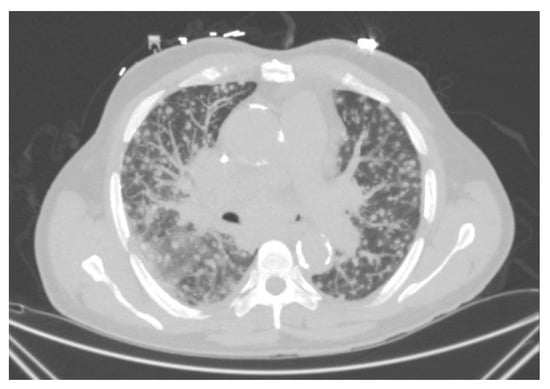

Symptoms are usually non-specific and may include fever, fatigue, and weight loss. Pulmonary symptoms may not be predominant and can include a dry cough and shortness of breath. Pulmonary imaging can show diffuse miliary-type reticulonodular infiltrates (Figure 8). Patients may present with hepatosplenomegaly, extrapulmonary lymphadenopathy, CNS lesions, and skin lesions. Gastrointestinal involvement is common and may mimic a cytomegalovirus infection. It can present with diarrhea, mucosal thickening, and ulcerations. Laboratory analysis may show cytopenia, hepatic enzyme elevation, and high lactate dehydrogenase.

Figure 8.

Progressive disseminated histoplasmosis. CT chest showing diffuse reticulonodular infiltrates with large mediastinal lymphadenopathies.